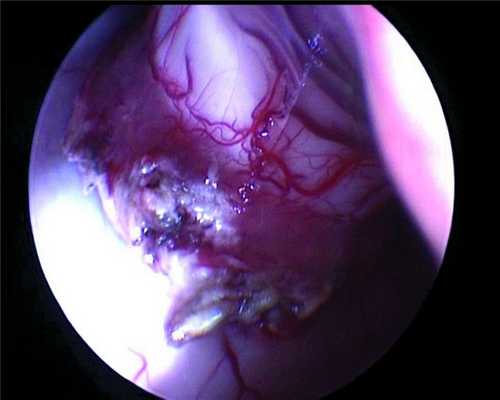

Данные нейросонографии изменили хирургическую тактику — доступ к опухоли был осуществлен транскортикально через теменную долю к области желудочкового треугольника с кортикотомией до 1 см. На глубине 2 см вскрылся правый боковой желудочек, в рану под давлением стал поступать ликвор, в правом боковом желудочке обнаружилось новообразование розового цвета, по виду типичная хориоидпапиллома (рис. 3).

Рисунок 3. ПСС — момент осмотра патологического образования и анатомических структур, прилежащих к нему. Эндоскоп 30°. Удаление образования начато с помощью биполярной коагуляции, отсоса и микроножниц.

Новообразование занимало большую часть тела правого бокового желудочка, исходным местом роста являлось сосудистое сплетение. Проведена инспекция тела правого бокового желудочка при помощи эндоскопа 30°, выявившая длинную сосудистую ножку, исходящую из задней хориоидальной артерии (рис. 4),

Рисунок 4. Питающая опухоль сосудистая ножка — вид через оптику эндоскопа 30°. которая прокоагулирована и отсечена при помощи микроножниц.

При эндоскопической инспекции височного рога обнаружены дополнительные артерии, подходящие к опухоли, которые также были прокоагулированы и отсечены при помощи микроножниц. После этого остаточные части опухоли, располагавшиеся в задней части правого бокового желудочка, были легко удалены. Опухоль не инфильтрировала окружающую мозговую ткань, и при эндоскопической инспекции желудочковой системы остатков опухоли обнаружено не было. Контроль гемостаза и наличия остатков опухоли произведен с помощью эндоскопической оптики 0, 30° (рис. 5).

Рисунок 5. Ложе удаленной опухоли — контроль гемостаза и радикальности удаления (область сосудистого треугольника). Эндоскоп 0°.